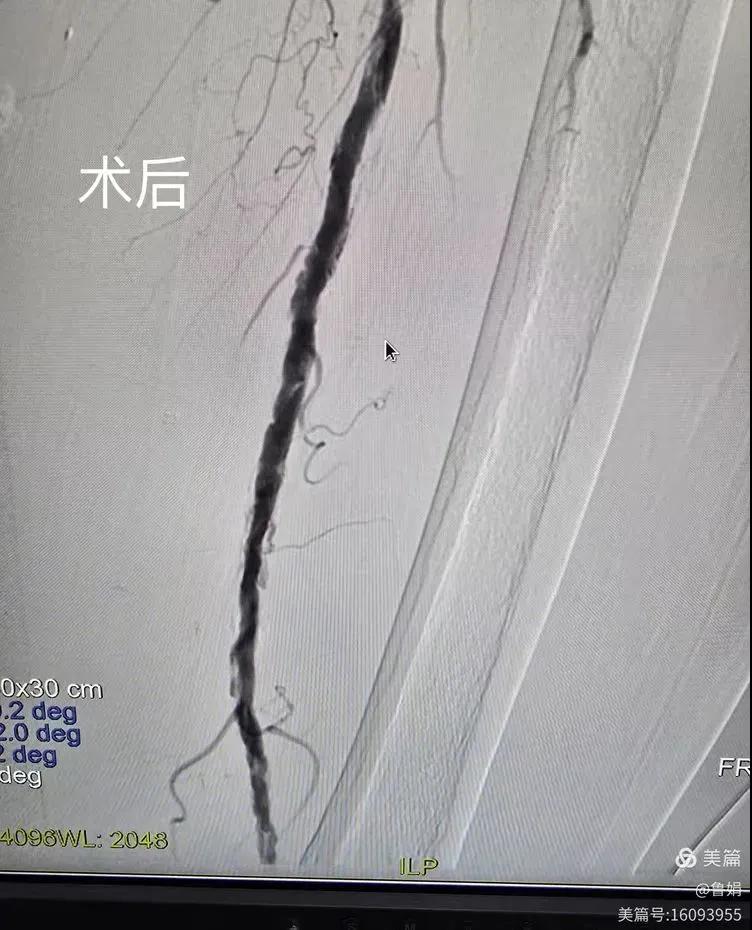

據(jù)悉,該患者,女,73歲,下肢動脈硬化閉塞癥,“以靜息痛,間歇性跛行”入院,CTA評估:股淺動脈,腘動脈間斷性多段重度狹窄,外二科血管外科團(tuán)隊根據(jù)患者病情,結(jié)合檢查結(jié)果,經(jīng)過科室會診后,決定對該病人行介入治療。手術(shù)由周創(chuàng)業(yè)副主任與北大一院血管外科專家郭宏杰教授聯(lián)合開展,對股淺動脈,腘動脈重度閉塞段行血管開通+藥涂球囊擴(kuò)張成形,術(shù)后狹窄明顯緩解,血流恢復(fù)!

下肢動脈閉塞的介入開通是外周介入領(lǐng)域難度最大的技術(shù)之一,這項微創(chuàng)介入手術(shù)的開展,實現(xiàn)了漯河市中醫(yī)院在下肢動脈血管介入治療上零的突破,進(jìn)一步推動了醫(yī)院介入治療技術(shù)的發(fā)展,讓患者足不出戶就能切實享受到優(yōu)質(zhì)的醫(yī)療資源,極大方便了患者就醫(yī)。(介入中心:魯娟)